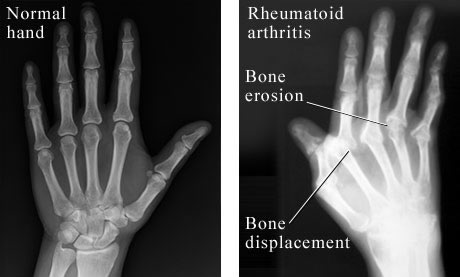

Figure 2. This image shows the contrast of an X-ray of a normal hand on the left to that of a patient with RA on the right. This inflammation, bone errosion, and bone displacement is shown  in the right side of the figure. Permission pending from Paul Traughber of Intermountain Medical Imaging at http://www.webmd.com/hw/health_guide_atoz/zm6061.asp.